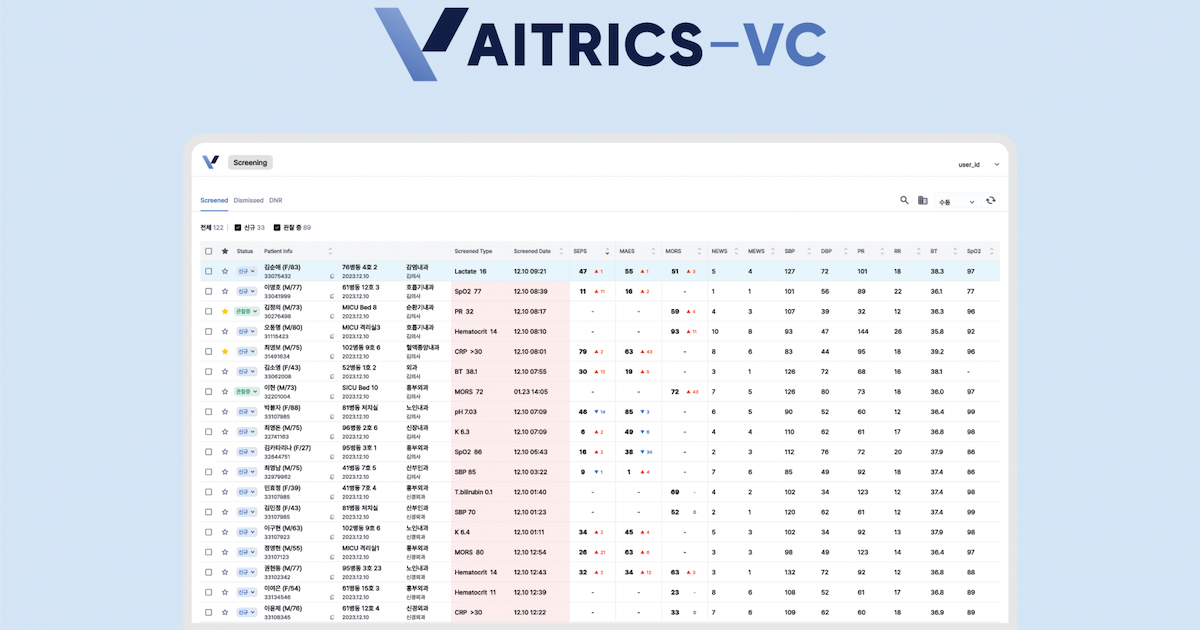

Another Korean company, Coreline Soft, bagged contracts in Europe to supply its AI screening software.

Following a competitive bidding process, it will provide the University Hospital Lausanne in Switzerland with its flagship product, AVIEW LCS Plus, which uses AI to identify lung nodules, pulmonary emphysema, and coronary artery calcification in chest X-rays.

The same software is also being implemented in the respective lung disease research of two French hospitals, the Bichat–Claude Bernard Hospital under Europe's largest hospital system, Assistance Publique–Hôpitaux de Paris, and the private, not-for-profit Foch Hospital in Suresnes, a commune in western Paris.

Hospital del Mar, a general hospital in Barcelona, Spain, is also adopting Coreline's AI screening tool for its clinical research on lung cancer. The hospital is part of the European lung cancer screening project, 4-In-The-Lung-Run, of which Coreline is also a technology partner.